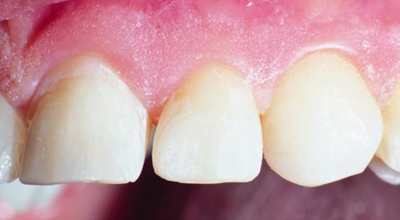

首先:用Peak Universal Bond和復(fù)合樹脂關(guān)閉鄰間隙并輕微矯正牙位??諝廨p吹,光固化20秒。

在修復(fù)和拋光后,酸蝕5秒,用PermaSeal封閉復(fù)合樹脂表面并完成表面拋光。